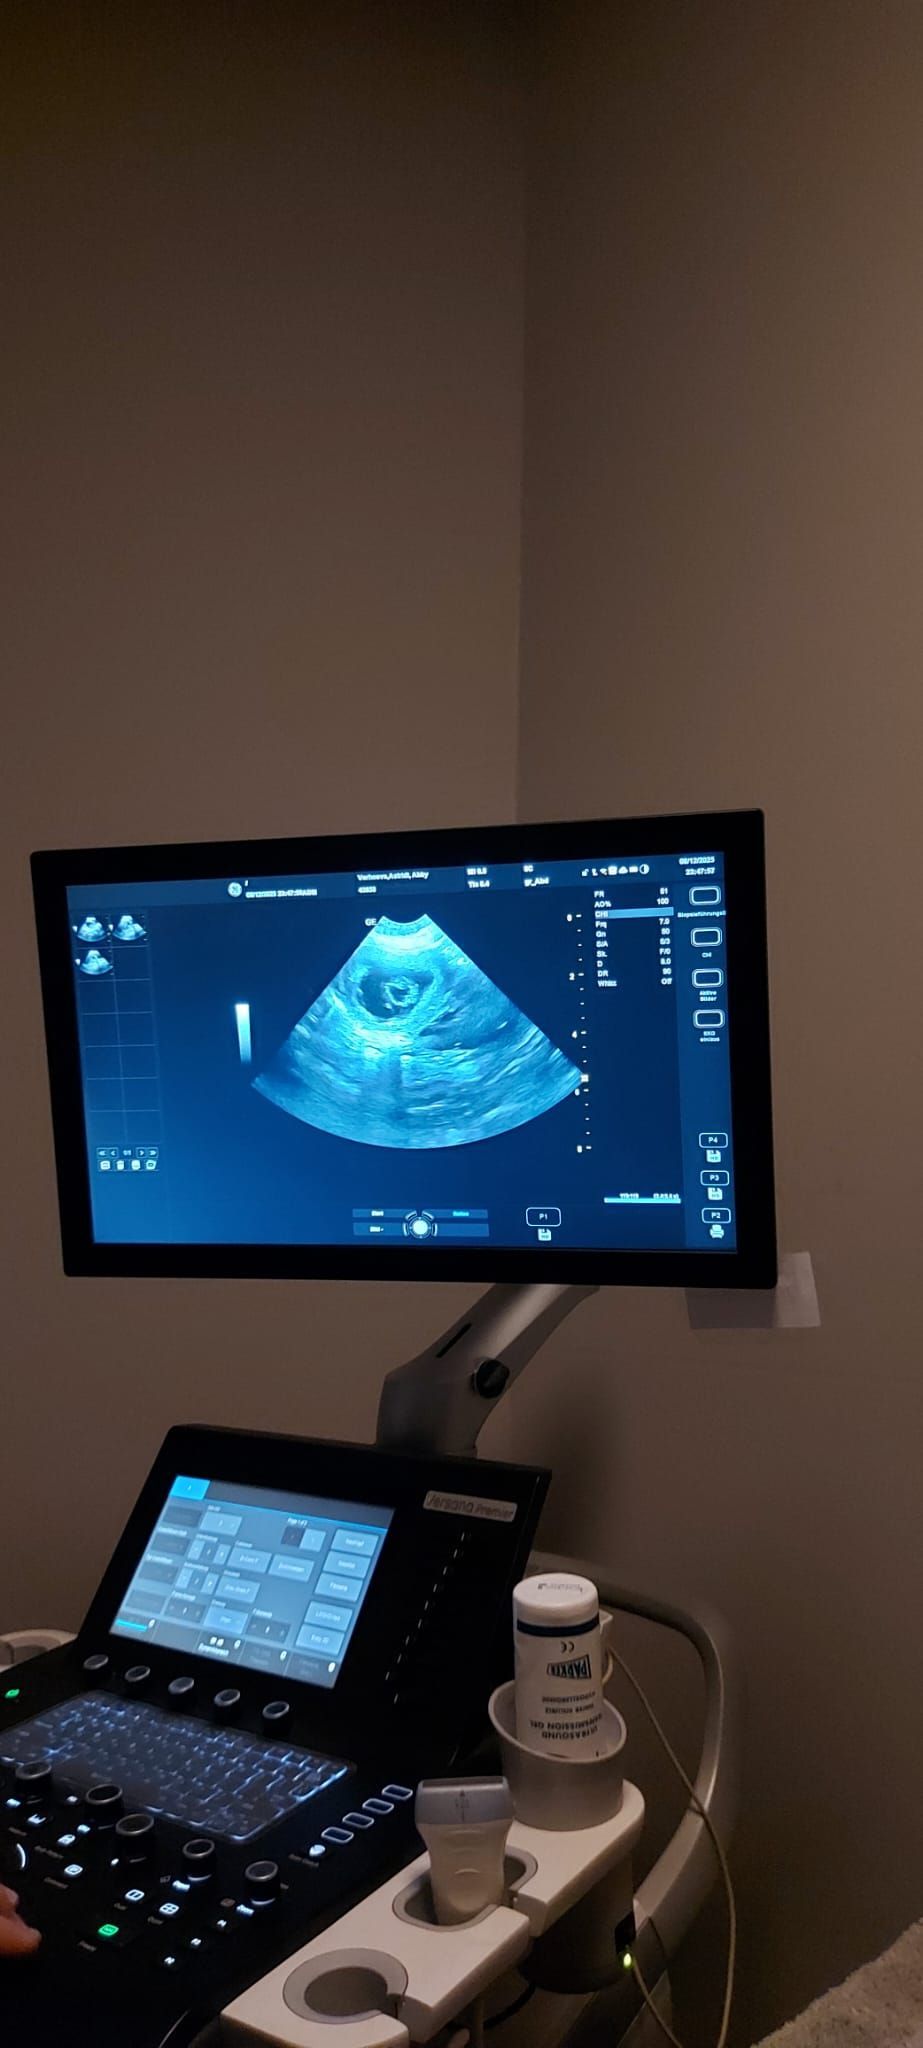

Gestern, genau 31 Tage nach dem Deckakt, stand für unsere Abby ein besonderer Termin an: Wir fuhren zu unserem Tierarzt Dr. med. vet. Andreas Bücheler, um nachzusehen, was sich in ihrem Bauch tut.

Zuerst ging es auf die Waage: Abby hat 550 Gramm zugelegt, was Andreas sofort positiv stimmte. Danach folgte der spannende Teil – der Ultraschall. Abby musste sich dafür auf den Rücken in eine spezielle Halterung legen, was normalerweise gar nicht ihr Ding ist. Doch diesmal überraschte sie uns: Sie legte sich ruhig hin und schaute mich dabei direkt an, als wollte sie sagen: „Na gut, ich mach das jetzt für euch.“

Als Andreas das Ultraschallgerät ansetzte, war seine erste Bemerkung ein fröhliches „Full House!“ 😊. Mit einem Lächeln erklärte er uns, dass da wohl einiges auf uns zukommt. Er prüfte sorgfältig, ob alle Welpen im Bauch gesund aussehen, und bestätigte schließlich: „Das sieht alles sehr gut aus.“

Natürlich hat er uns auch die genaue Zahl verraten – doch die behalten wir noch für uns. Denn bis zur Geburt kann leider noch viel passieren, auch wenn wir alles tun werden, um Abby bestmöglich zu unterstützen.

Wenn alles weiterhin so gut verläuft, dürfen wir uns in der zweiten Januarwoche auf die Ankunft kleiner Kromis freuen. Ein aufregendes Abenteuer beginnt – und wir können es kaum erwarten, die neuen Familienmitglieder willkommen zu heißen.